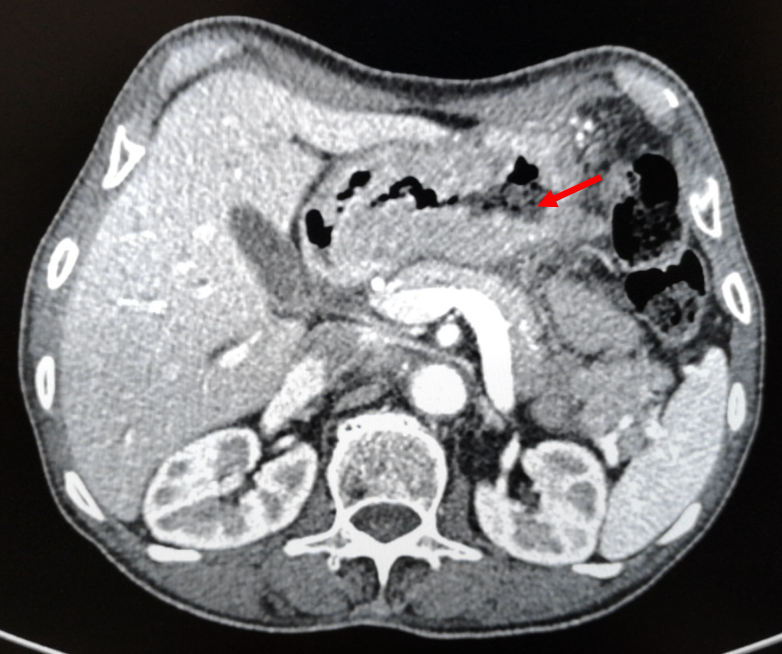

腹盆腔强化CT(2018-4-4):1、胃体及胃窦胃壁增厚,考虑胃癌;2、胃周、胃左动脉区及腹膜后多发肿大淋巴结,考虑转移;3、肝内胆管结石,肝内胆管轻度扩张;4、左肾囊肿,左肾上腺增厚,考虑增生;5、前列腺增生伴钙化;6、盆腔少量积液;7、两下肺实变索条,左侧胸腔少量积液。

图1-2 2018-4-4 箭头为胃部肿瘤,胃壁增厚明显